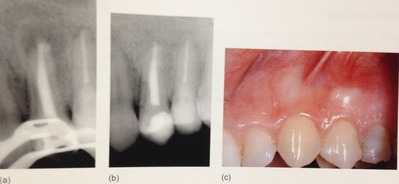

先日に書いたように完全に細菌を取り除くことはできません。

ので、外科的な治療が必要な歯もあるんです。

こんなに大きな穴でも、治ります。

少し根っ子を削るので、短くはなりますが。